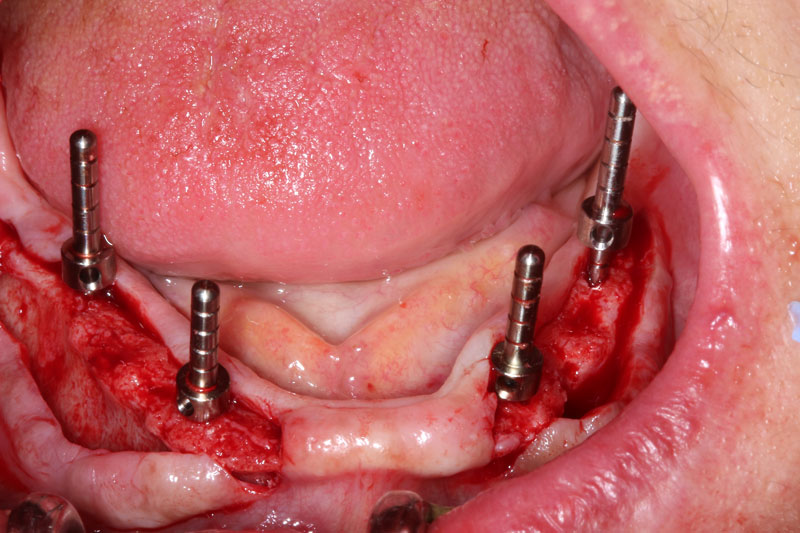

Στο δευτερο μέρος παρουσιαζεται το χειρουργικο σχεδιο θεραπειας στην αποκατάσταση του ασθενους με εμφυτευματα καθώς και τακτικες τοποθετισης εμφυτευματων σε διαφορες περιπτωσεις κλινικών προβληματων.

1. Βασικες αρχές στο χειρουργικό σχέδιο θεραπείας στην εμφυτευματολογία

–υλοποίηση του χειρουργικού σχεδίου

2. προσεγγίσεις και χειρουργικές τεχνικές σε αποκατάσταση μονήρων

δοντιών άνω και κάτω γνάθου.-άμεση τοποθέτηση –διατήρηση φατνιακού

όγκου

χειρουργικές λύσεις στην αποκατάσταση μερικής η ολικής νωδότητας άνω –

κάτω γνάθου

Hands on τοποθέτηση x2 εμφυτευμάτων Paltop

σε μοντέλο πλαστικής γνάθου.

- Διατήρηση φατνιακής ακρολοφίας – βασικό χειρουργικό σχέδιο στη τοποθέτηση εμφυτευμάτων –(αρχές σχεδίου θεραπείας- εκτίμηση απεικονιστικών μεθόδων).

- Βασικές χειρουργικές τεχνικές και αρχές στη τοποθέτηση των εμφυτευμάτων και ανάπλαση ελλειμματικής φατνιακής ακρολοφίας μικρού η μέσου βαθμού.